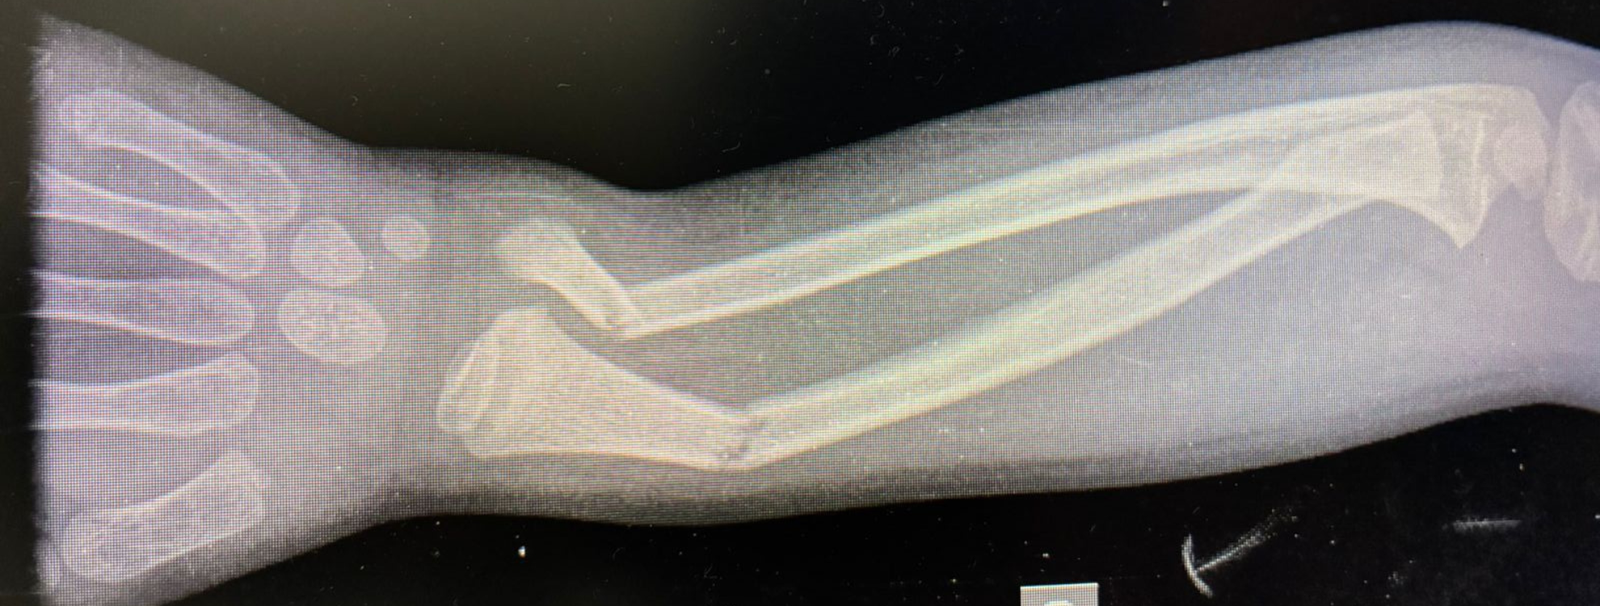

Fratura em “galho verde”

Os ossos das crianças são naturalmente mais flexíveis e elásticos do que os dos adultos. Por isso, em algumas quedas ou impactos, o osso não se parte completamente. Em vez disso, ele se dobra e apresenta uma fratura parcial em apenas um dos lados, situação conhecida como fratura em “galho verde”, em referência ao que acontece ao tentar quebrar um galho ainda verde de uma árvore.

Apesar de não haver separação total do osso, essa fratura não deve ser subestimada. O membro pode ficar visivelmente curvado, e sintomas como dor, inchaço e limitação do movimento indicam que houve uma lesão que precisa ser avaliada.

Em alguns casos, a curvatura é aceitável e o tratamento pode ser feito apenas com imobilização em gesso. Em outros, é necessário realinhar o osso antes da imobilização para garantir que a cicatrização ocorra na posição correta.